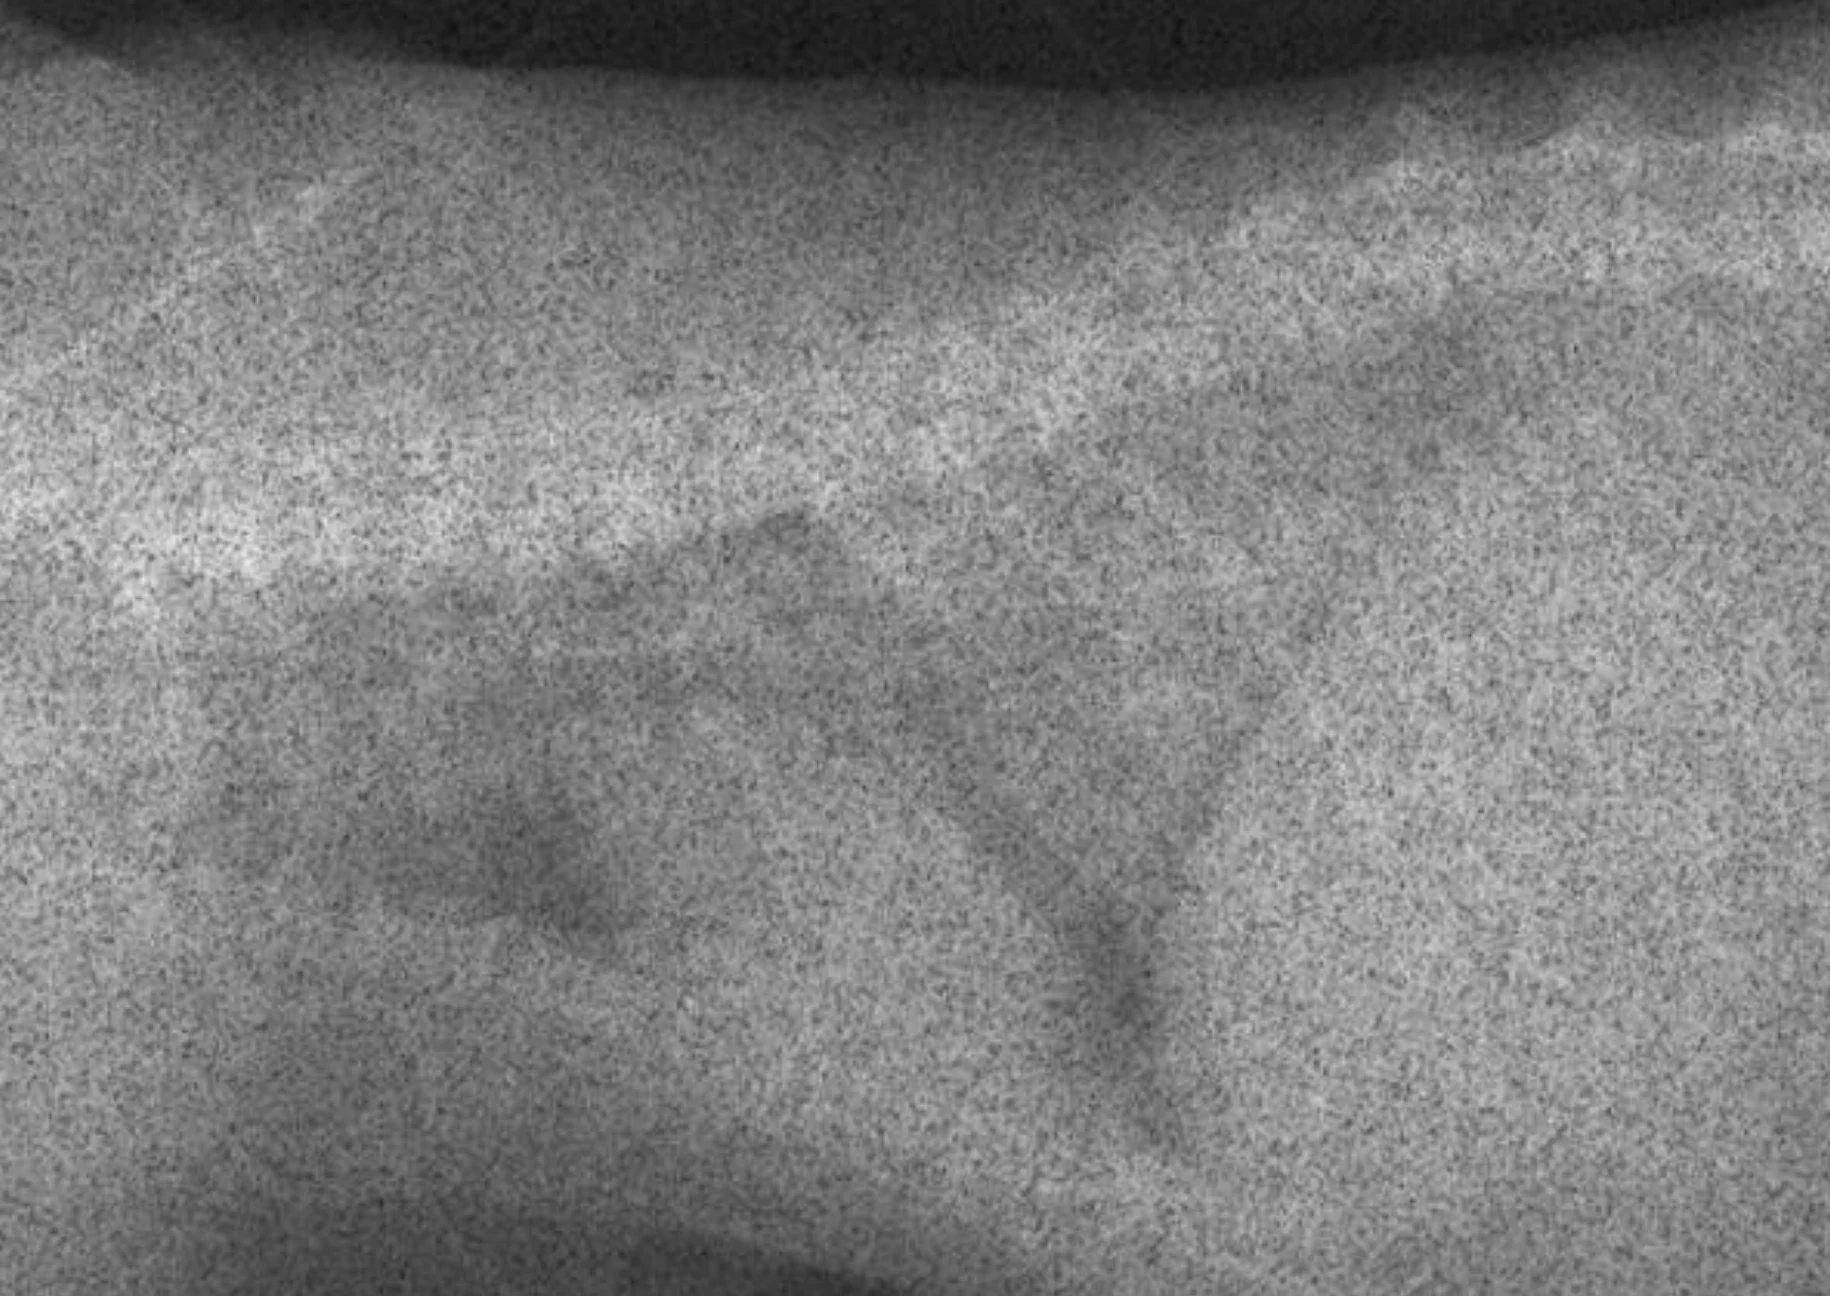

In most cases, an overexposed radiograph will have soft tissue that cannot be seen, even with adjustments in brightness (window/level). In Figure C, the digital image is overexposed, which results in inability to see the lung in the cranioventral thorax and between the heart and diaphragm; this area will remain black with increases in brightness. The technique has been corrected in Figure D.